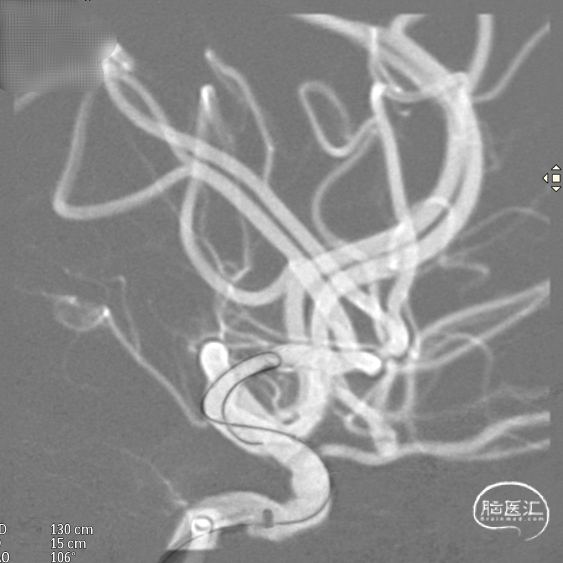

支架到位,远端打开(正侧位):4.75-20mm支架在大脑中动脉M1段打开,回撤至C6段远端锚定。支架释放过程中,轻柔推送支架系统,可见支架导管沿血管壁大弯侧走行,支架打开良好。

支架中段打开: